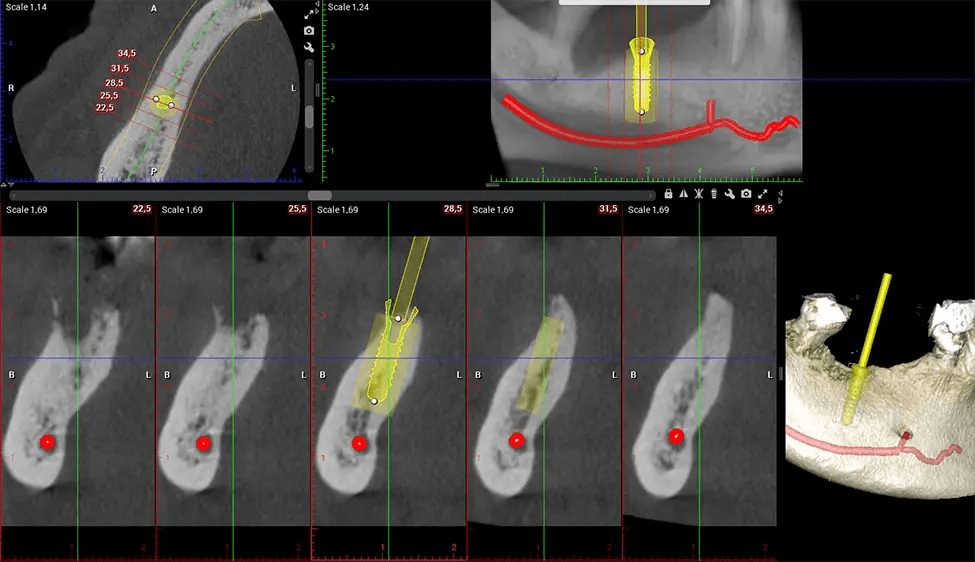

Cuando se combina con extracciones, colocación de implantes dentales o injertos óseos, la tecnología CBCT puede brindarle una experiencia más rápida y mucho más cómoda. Esto se debe a que la imagen 3D proporciona una imagen más detallada de toda su cavidad bucal, lo que le permite a su dentista guiarlo en cada paso del proceso antes de que ocurra. Esto a menudo ayuda a los pacientes a sentirse más preparados y cómodos en general, especialmente si han tenido una experiencia traumática con tratamientos dentales anteriores.

Después del proceso de escaneo, las imágenes de rayos X capturadas son procesadas por el software CBCT, que aplica algoritmos para reconstruir una imagen 3D detallada del área escaneada. El software recopila estas imágenes de rayos X individuales y crea una representación digital en 3D de la anatomía del paciente. El dentista o el radiólogo pueden ver y analizar la imagen CBCT 3D reconstruida. Esta imagen se puede manipular, rotar y acercar o alejar para examinar estructuras específicas y evaluar la condición del paciente.

Planmeca Viso G7 CBCT (Cone Beam CT Scan) está diseñado para superar las demandas de los líderes de la industria, los especialistas y las grandes instituciones. Tiene un gran sensor de ø25×30 cm con cuatro cámaras integradas. Puede capturar tamaños de volumen ilimitados, desde ø3×3 cm hasta ø30x30cm, capturando el casquete escutelario a través de C7 en la columna cervical. Planmeca Viso G7 ofrece el escaneo de volumen único más grande de la industria de ø30×19 cm. Está preparado para manejar modalidades de imágenes avanzadas como la tecnología Planmeca ProFace® y Planmeca 4D™ Jaw Motion. El soporte occipital para la cabeza permite una visión sin obstáculos del tejido facial.